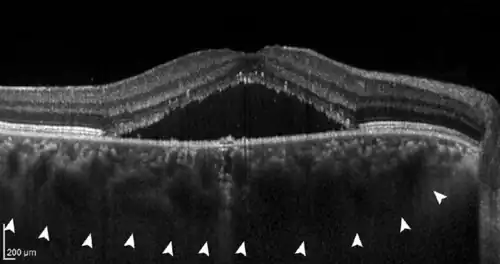

The disease mechanisms are not completely understood. All pachychoroid disorders of the macula show choroidal thickening and congestion with increased blood vessel diameter, especially in the deep choroid (the so-called Haller's layer). This results in increased pressure from the deep choroid against the superficial choroid close to the retina, damaging the fine blood vessels (capillaries) needed to supply oxygen and nutrients to the retinal pigment epithelium and retina. Additionally, fluid can leak from these damaged vessels and accumulate under the retina.[1][2]

- If further damage to Bruch's membrane and the pigment epithelium causes fluid to accumulate under the retina, central serous chorioretinopathy (CSC) develops. In this stage, patients often have blurred vision and report a reduction in visual acuity with perception of a central "grey spot". In the majority of patients, spontaneous resolution of the subretinal fluid occurs within a few months, but recurs in up to 50% of cases. In some patients the fluid remains, making it a chronic disease; medical therapy or the application of various laser methods is possible.